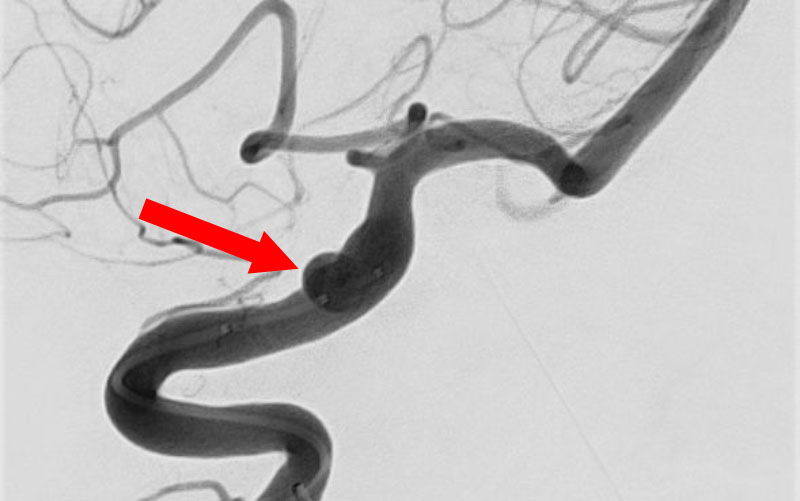

No.1630 手術前